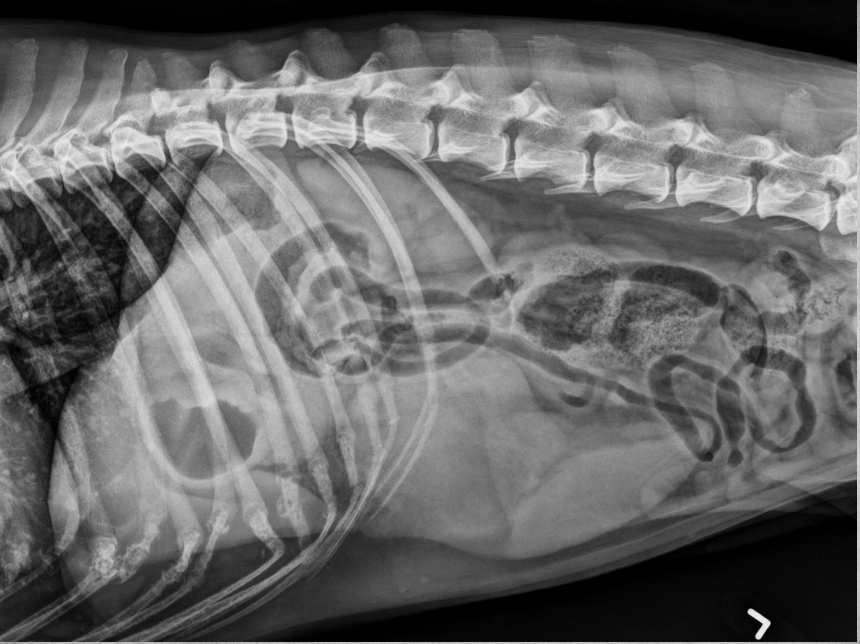

●9 yo mixed breed female dog

(sterilized)

●Increased ALP

● Impressive amount of subcutaneous and intra-abdominal fat.

● Enlarged liver – changed gastric axis pushed caudally, rounded edges, extending past the costal arch.

● At least two round soft tissue opacity structures superimposed on ventral liver (lateral view).

● Round soft tissue structure cranial to right kidney.

● Mass in adrenal gland or pancreas

● Hepatic nodules (benign vs metastatic disease)

SI gas is normal because bowels empty.